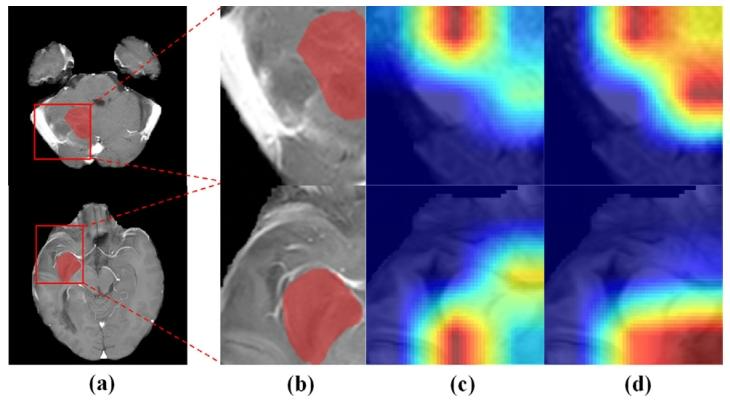

Fig. 6. (a) Origin T1C MRI images. (b) Amplified rectangular ROI with HRA regions(red region). ©/(d) Regions captured by using the proposed method without/with thedual-focus fusion module

图6 (a)原始T1增强(T1C)MRI图像;(b)含高风险复发区域(HRA,红色区域)的矩形感兴趣区域(ROI)放大图;(c)/(d)所提方法在未使用/使用双焦点融合模块时捕捉到的区域。